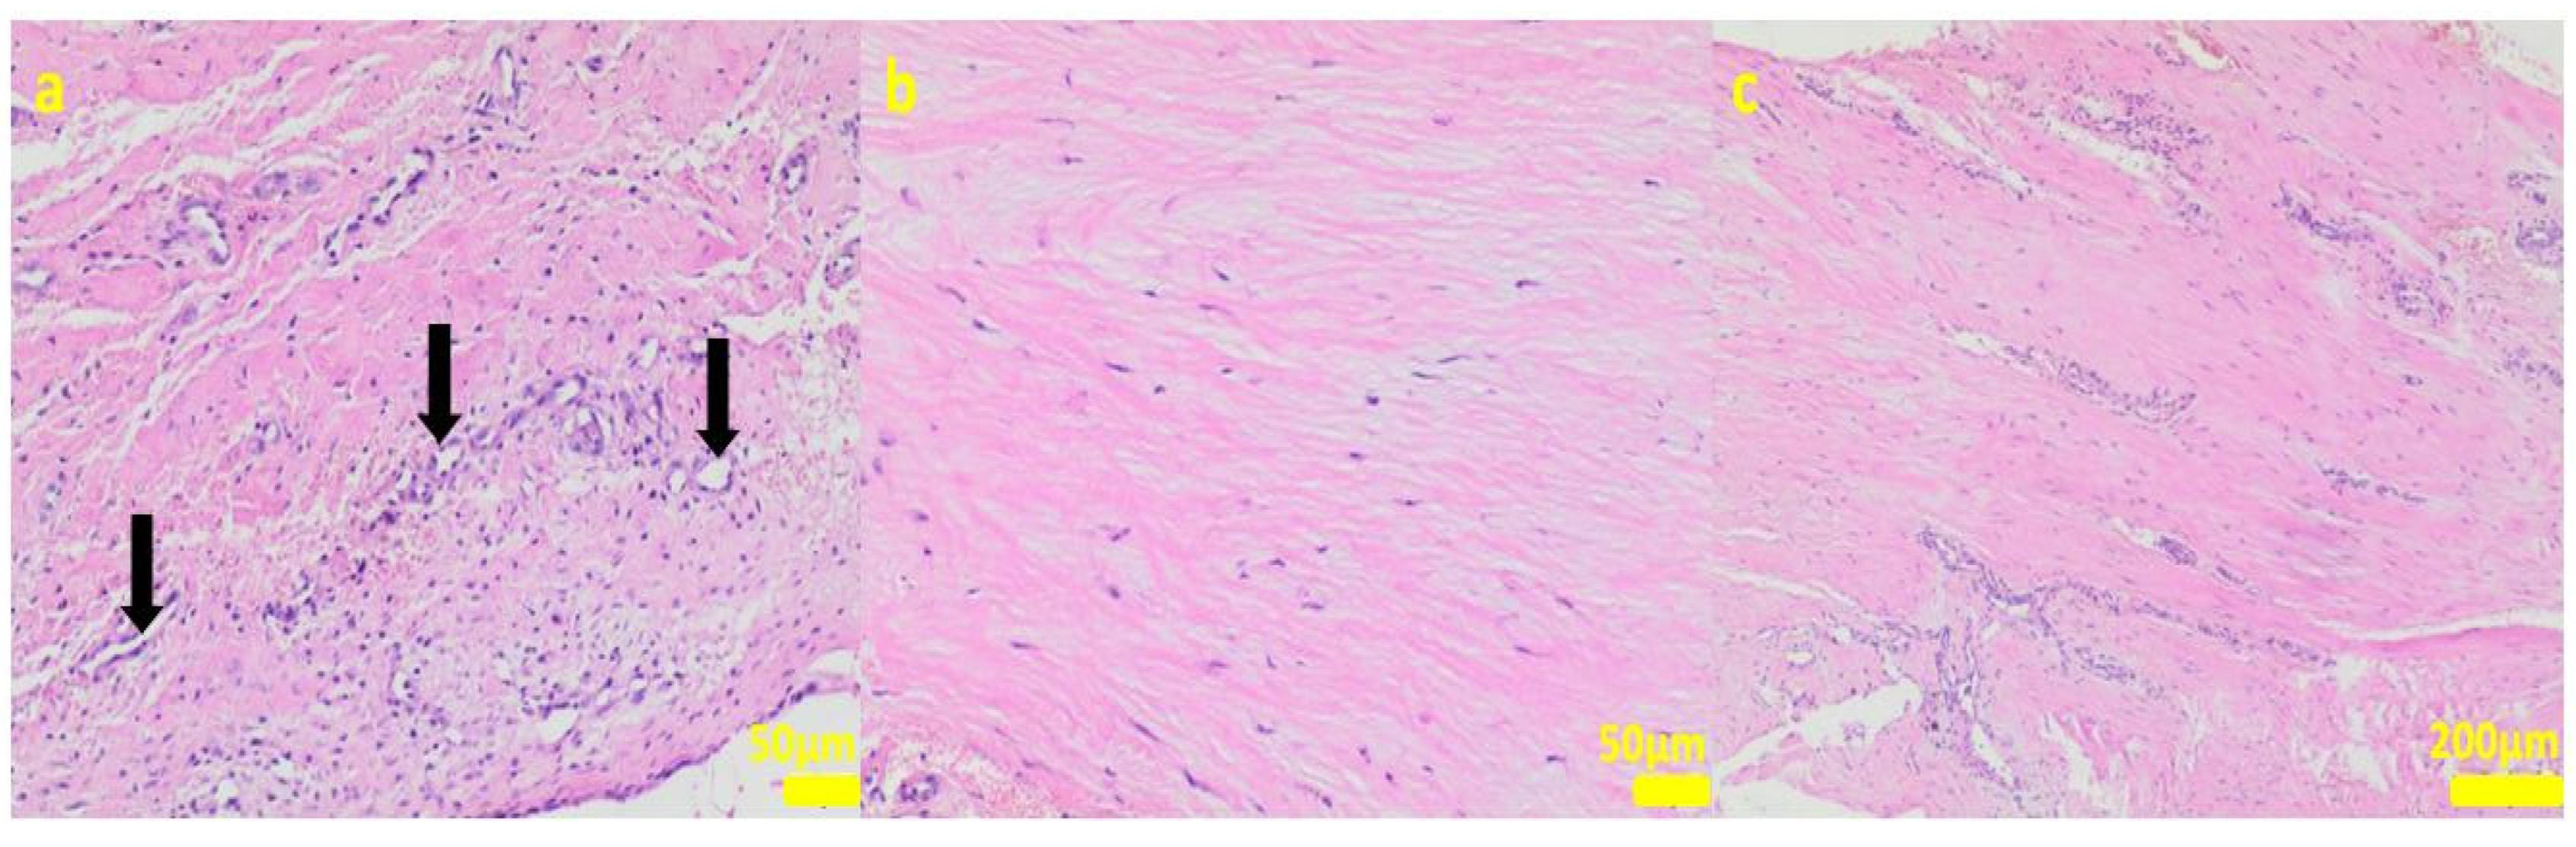

During the removal procedure, the implant proved to be very well-adhered to the tissue. The microscopic examinations of the collected samples (all the tissues collected after 3 months of implantations from the implant/bone contact area; each sample from the different patient) did not reveal microorganisms. Moreover, there was no inflammatory response suggesting a bacterial infection (Figure 6, Figure 7, Figure 8, Figure 9 and Figure 10). Although inflammatory infiltrates were found, they were more typical for a foreign body reaction (granulomatous inflammation in sample 1) or a chronic antigenic stimulation (plasmocytic infiltrate in sample 6).

Figure 7.

Sample 2:at the sample periphery, the fibrous connective tissue abundant in cells and small blood vessels (black arrows, (a)) with areas of maturation to compact fibrous tissue (b,c). Hematoxylin-eosin staining, magnification 200× (a,b), 40× (c).

The microscopic lesions observed in the examined samples suggested the correct tissue reparation process, starting from the granulation tissue up to the mature compact fibrous tissue that is typical for postsurgical scars. The implant, i.e., the TPLO plate and screws covered in the hybrid layer containing silver nanoparticles, seemed to facilitate the healing process; therefore, some features of granulomatous inflammation and plasmocytic perivascular infiltrates were present in the examined samples. Generally, both such microscopic findings and soft tissue calcification processes are observed in a natural healing process.